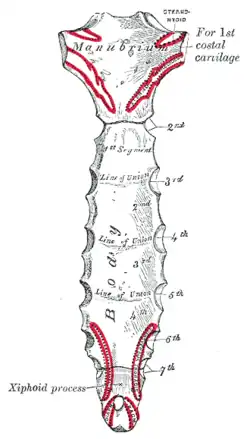

Superfície posterior do esterno. | |

Superfície anterior do esterno e cartilagens costais.

Superfície anterior do esterno e cartilagens costais. -